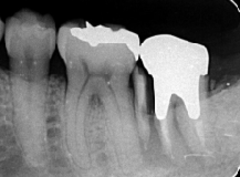

歯周病が進行し、グラグラして物が嚙めず、抜歯してインプラントにしていくことに。

インプラントはストローマンを使用、上部構造はジルコニアセラミックス